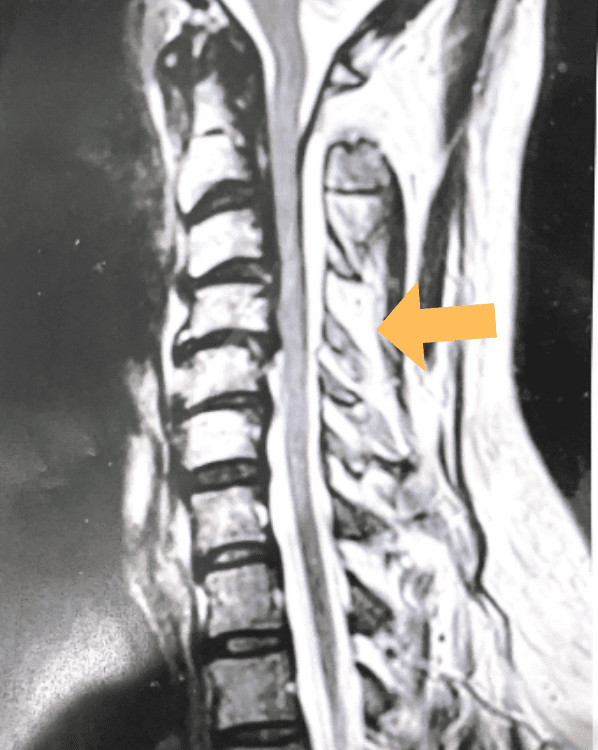

This 57 year-old male presents with severe neck, left shoulder and arm pain and weakness in his hand since being involved in a motor vehicle accident […]

Patient is a 60-year-old female who presents with severe right upper extremity pain and weakness over several months. She had a prior C6-7 ACDF with […]